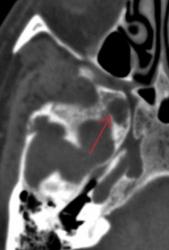

Метастазы в костях основания черепа.

Женщина средних лет с клиникой невралгии тройничного нерва справа. На КТ были выявлены округлые очаги деструкции в костях основания черепа (средней черепной ямки).

Наблюдение Nela.